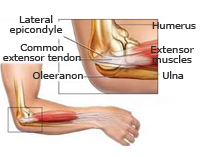

La articulación del codo está formada por las porciones inferior del húmero y superiores de cúbito y radio. Su lesión se produce fundamentalmente tras el impacto de la mano contra el suelo con el codo en extensión, siendo especialmente vulnerables los niños y la tercera edad. Tanto si existe rotura ósea (fractura) como si hay separación entre los huesos de la articulación (luxación) se requiere un diagnóstico eficaz y un rápido tratamiento para evitar la aparición de secuelas.

Fracturas de paleta humeral

La paleta humeral es la porción inferior del húmero que conecta con la parte superior del cúbito y radio formando la articulación del codo. Los traumatismos en esta región suelen producirse tras caída e impacto sobre la mano con el codo en extensión. Es necesaria una exploración neurovascular urgente para valorar lesiones en estructuras vasculares y nerviosas que pasan a este nivel y que se encargan del trofismo de la mano. El tratamiento se realizará en función del tipo de fractura y la edad del paciente con la finalidad de restituir, lo antes posible y sin secuelas, la funcionalidad de la articulación del codo.